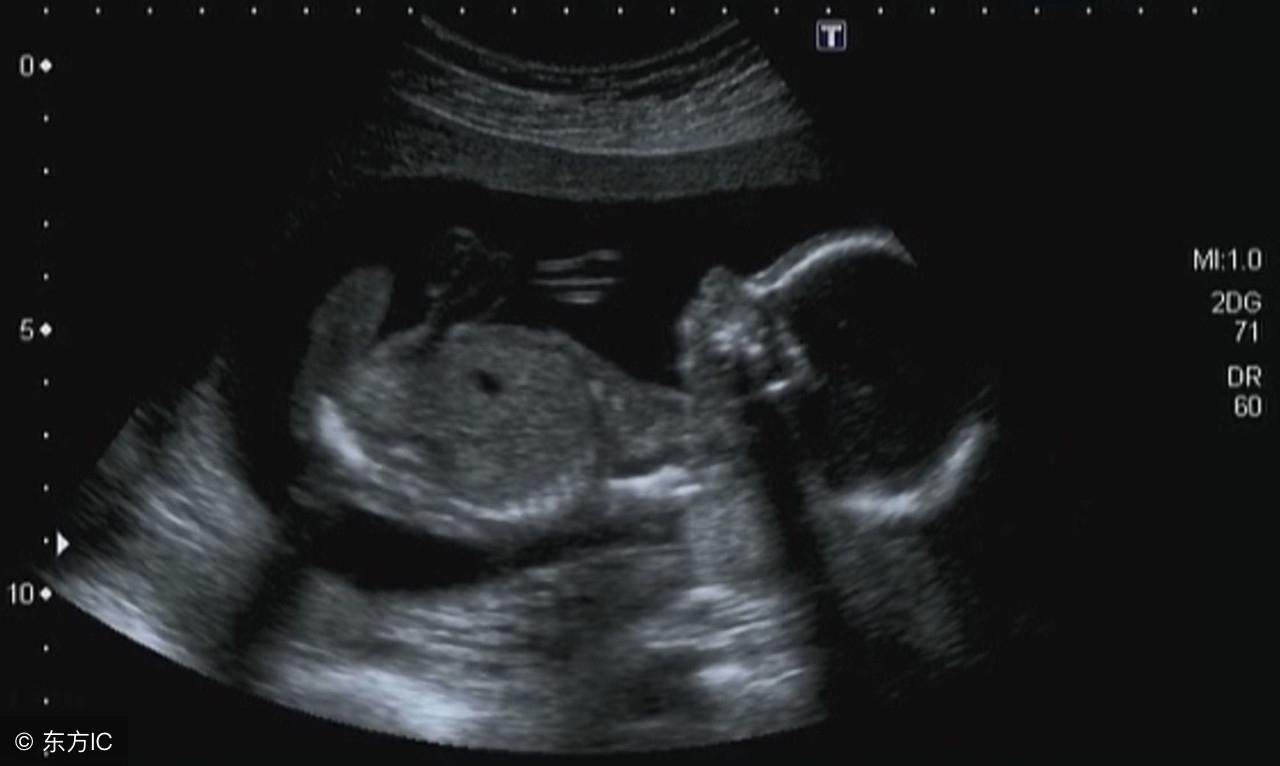

7周:胎儿长到1.33厘米,胚胎已具有人雏形,体节已全部分化,四肢分出,各系统进一步发育。B超清楚看到胎芽及胎心跳,胎囊约占宫腔的l/3。

8周:胎儿长到1.66厘米,胎形已定,可分出胎头、体及四肢,胎头大于躯干。B超可见胎囊约占官腔1/2,胎儿形态及胎动清楚可见,并可看见卵黄囊。

9周:胎儿长到2.15厘米,胎儿头大于胎体,各部表现更清晰,头颅开始钙化、胎盘开始发育。B超可见胎囊几乎占满宫腔,胎儿轮廓更清晰,胎盘开始出现。

10周:胎儿长到2.83厘米,胎儿各器官均已形成,胎盘雏形形成。B超可见胎囊开始消失,月芽形胎盘可见,胎儿活跃在羊水中 。

11周:胎儿长到3.62厘米,胎儿各器官进一步发育,胎盘发育。B超可见胎囊完全消失,胎盘清晰可见。

12周:胎儿长到4.58厘米,外生殖器初步发育,如有畸形可以表现,头颅钙化更趋完善。颅骨光环清楚,可测双顶径,明显的畸形可以诊断,此后各脏器趋向完善。